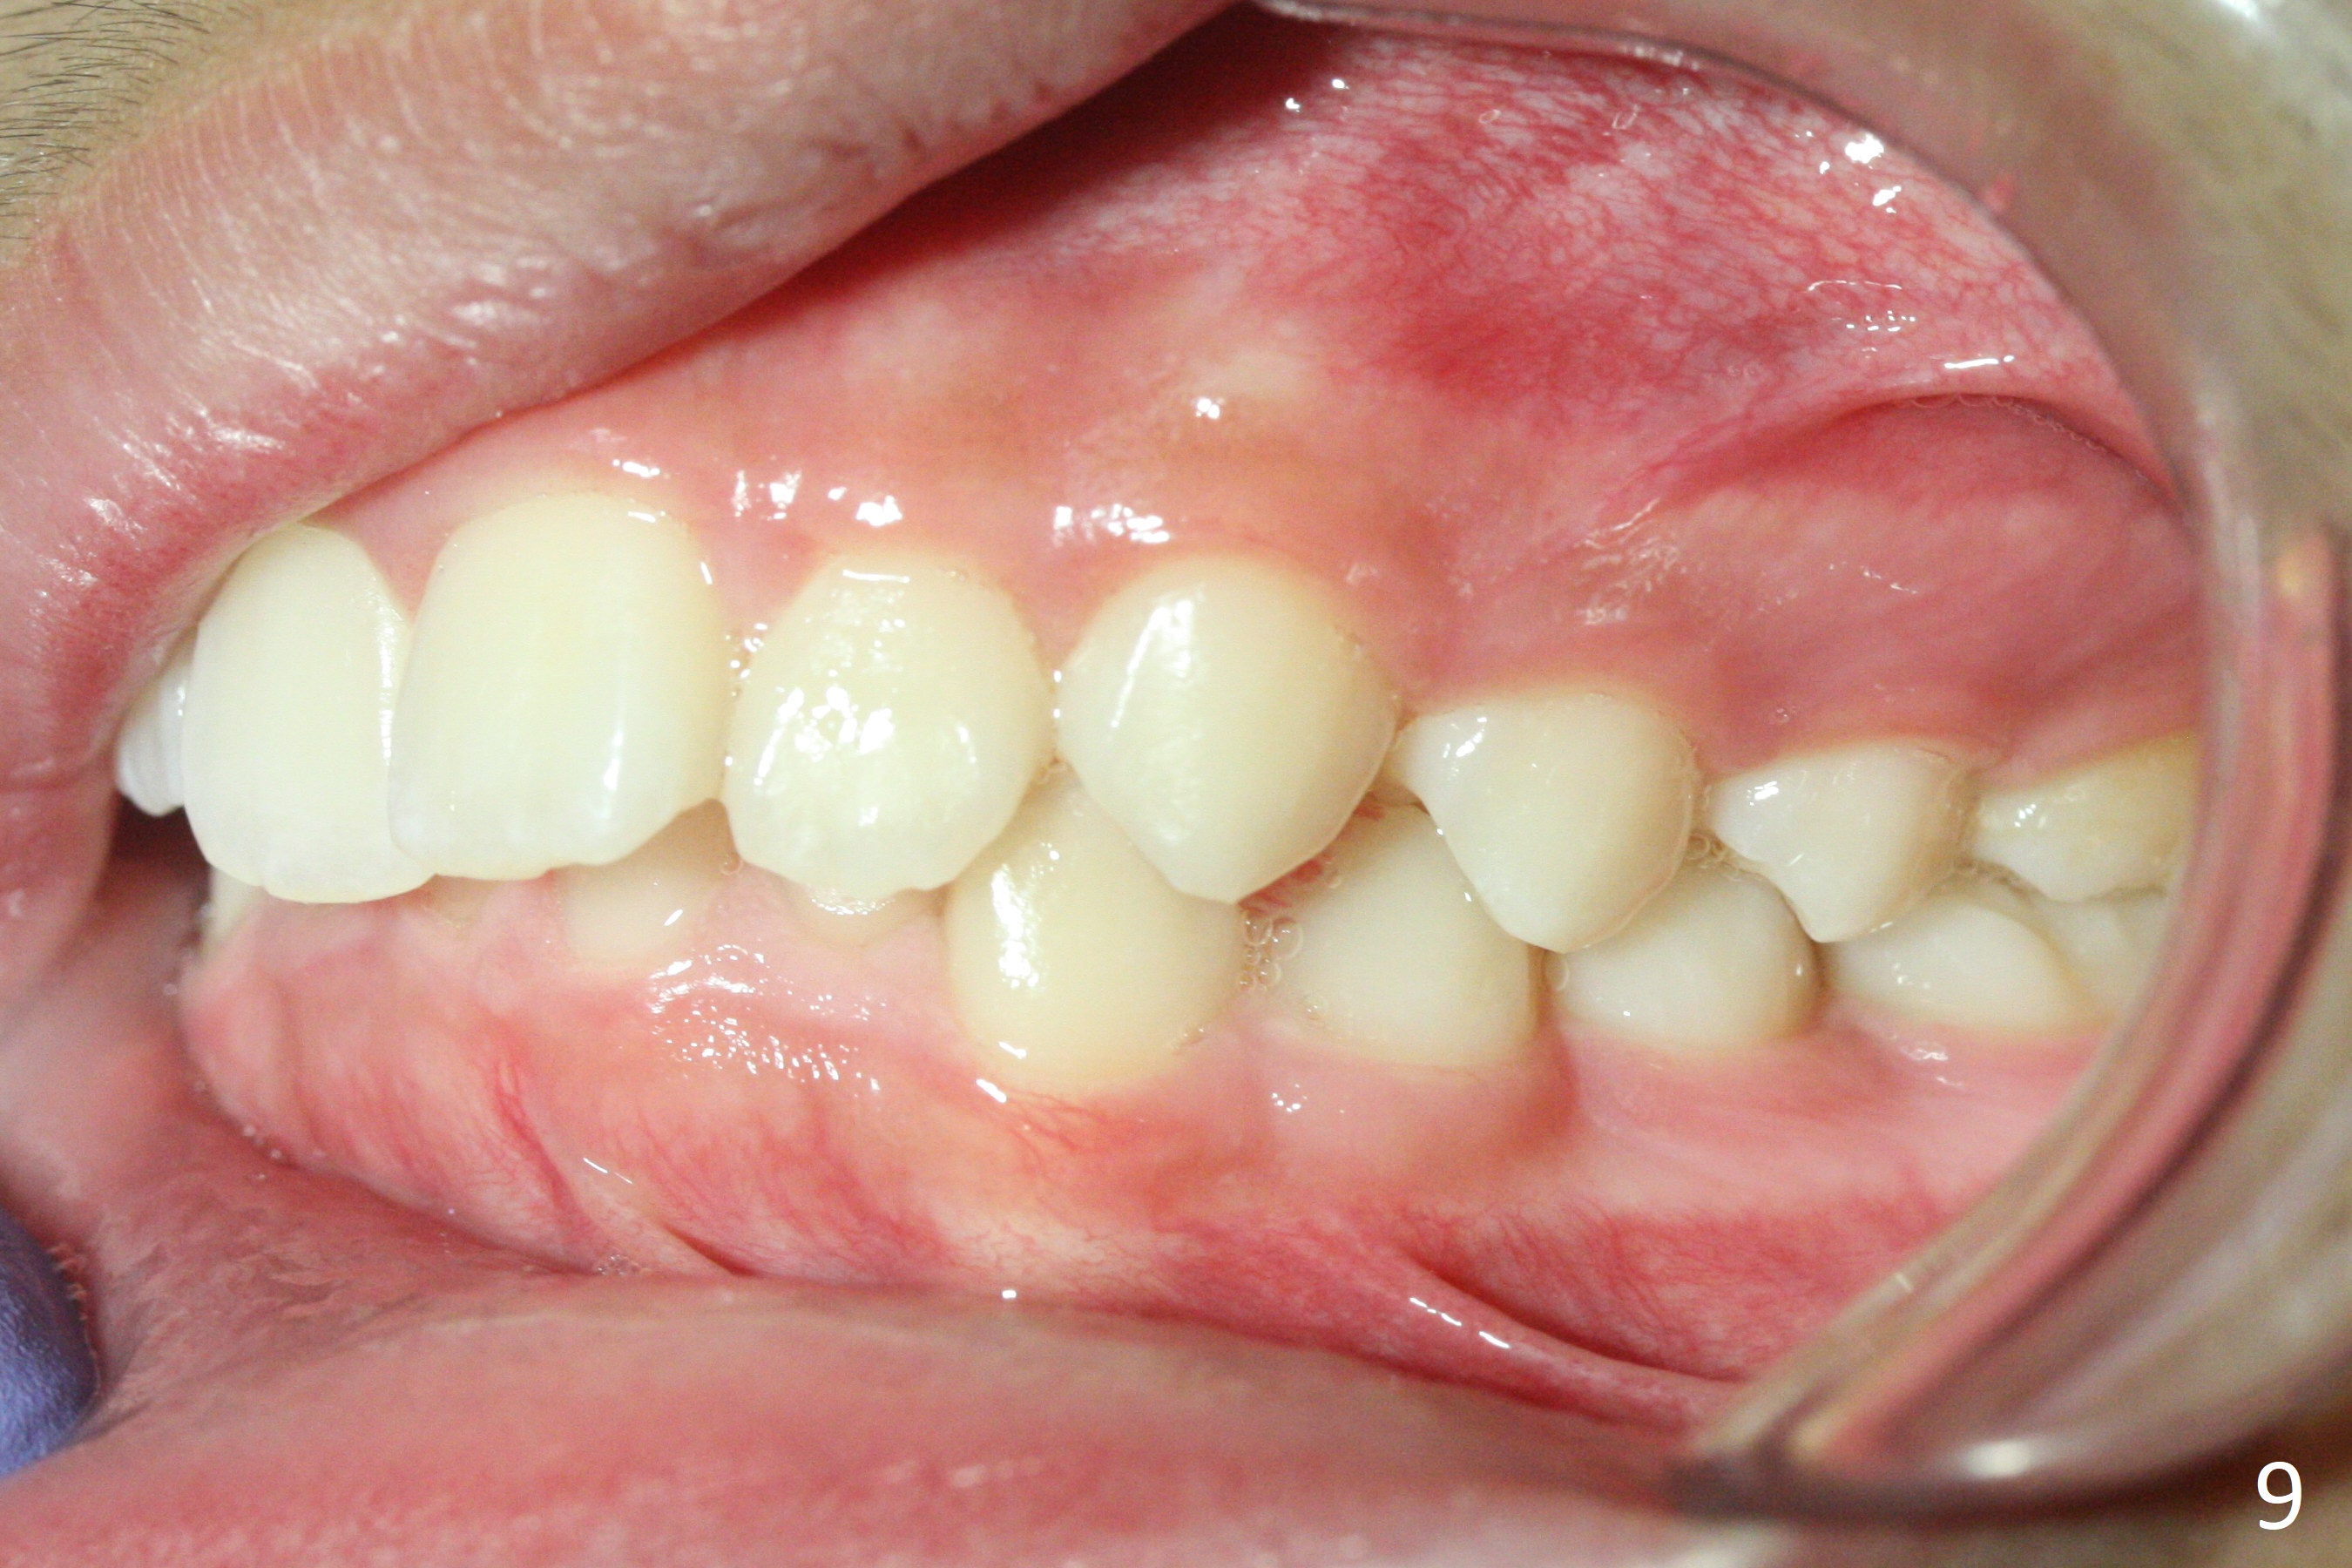

A 12-year-old woman has normal facial profile (Fig.1-6,12) and crowded dentition (7-11). Because of erupting 2nd molars (Fig.10,15), it is difficult to place rubber separators between U6/7. Copper ones are used instead (Fig.15 ^). Crowding and narrow arches (Fig.13,14) may be associated with the enlarged right Inferior Nasal Concha (Fig.15 *).